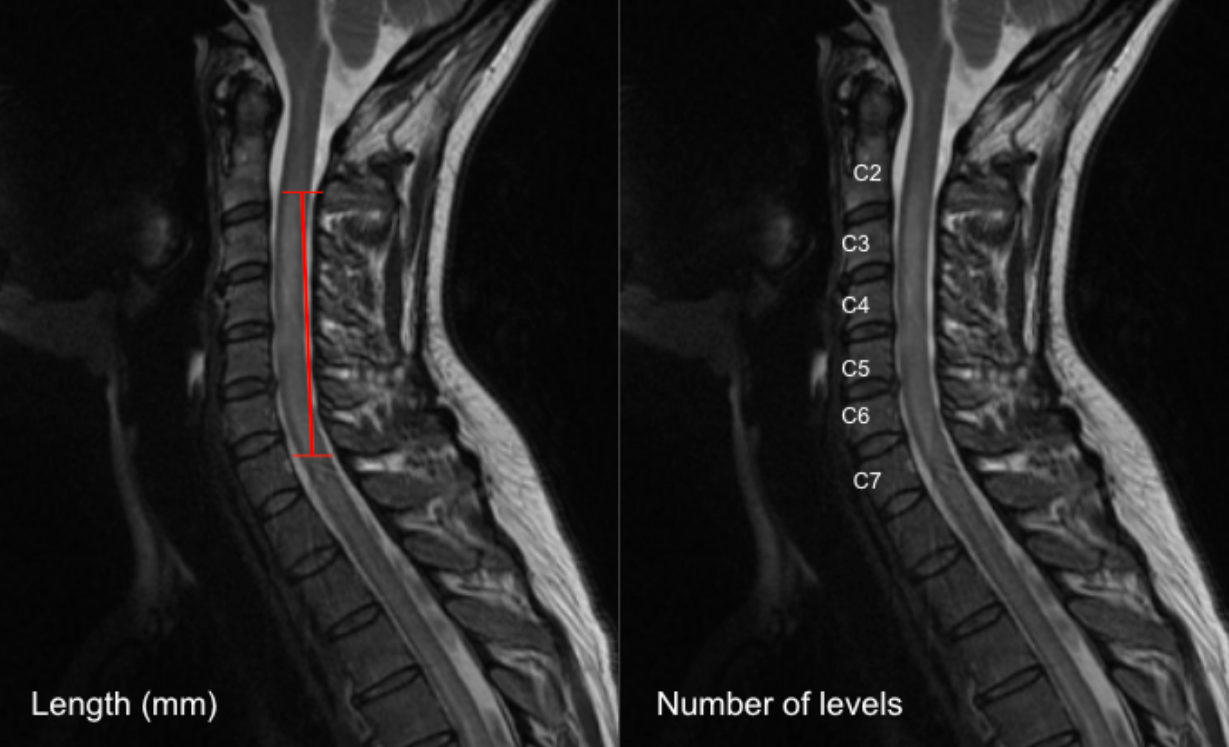

Option A: Linear Measurement (mm)

• Select a mid-sagittal T2-weighted MRI slice that best demonstrates the intramedullary hyperintensity.

• Identify the cranial (upper) and caudal (lower) margins of the T2 hyperintense signal within the spinal cord.

• Using digital calipers, measure the maximum craniocaudal length of the hyperintensity parallel to the long axis of the cord.

• Record the length in millimeters (mm).

Option B: Vertebral Level Count

•  On the same sagittal T2 image, identify the vertebral levels spanned by the hyperintense signal.

•  Count the number of vertebral body heights or disc levels involved (e.g., “C4–C6 = 2 vertebral levels”).

•  Partial involvement of a level may be recorded as 0.5 level, if desired.